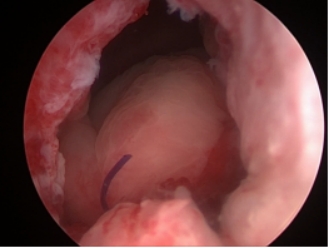

术中重建后膀胱颈变得宽大